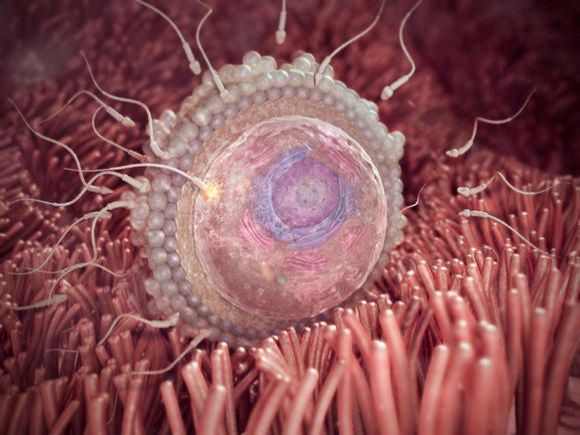

2. týden těhotenství

Maminka

V druhém týdnu těhotenství, ještě před tím, než se začne vyvíjet plod, vaše miminko, se musí připravit tělo. Od přírody je...